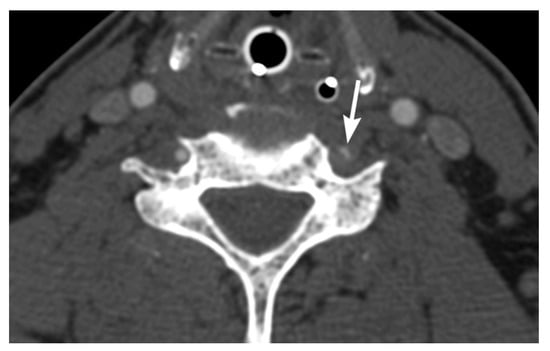

2. Imaging Techniques

3. Imaging Findings of Arterial Injury